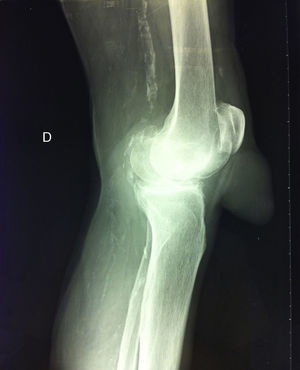

During radiological examination of the knee we observed that the tumor was of soft tissue in origin, showed no radiopaque images inside and respected the integrity of the patellar tendon. Other findings highlighted a degree of osteoarthritis and the presence of radiological signs of atheromatosis (Fig. 2).